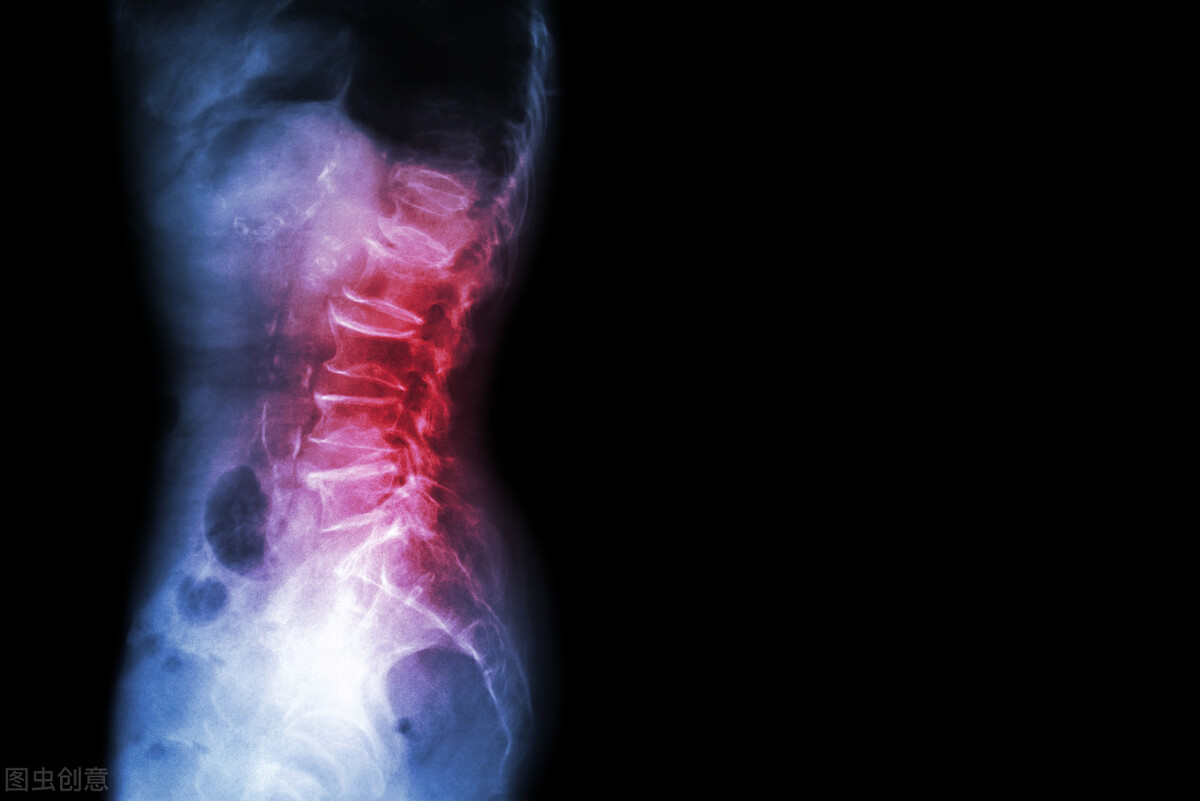

颈椎病是现代社会的常见疾病,伴随着现代电子化办公设备的普及,以及人们长期需要低头伏案工作,使用手机、iPad,或者电脑进行办公,加上我们颈椎天然的生理特性——由于它的活动度比较大,因此,发生的退变比较早,颈椎病发病率也在逐年上升。

先来说说第一类颈椎的轴性疼痛,颈椎轴性疼痛的患者会感到颈部后方出现僵硬感、无力感以及烧灼样的疼痛,是什么原因导致的呢?我们正常的颈椎有一个向前的生理弧度,就像一个弓箭,而我们的肌肉、韧带、血管、神经都走在这个弓的后方,就像弓箭和弓弦的关系。因此长期低头伏案工作的人,弓的正常弧度会变直,叫做颈椎的生理曲度变直,大家可以想象一下,后方的弓弦就会被迫拉长,长期处于疲劳状态,就是轴性颈椎病的一个主要成因。